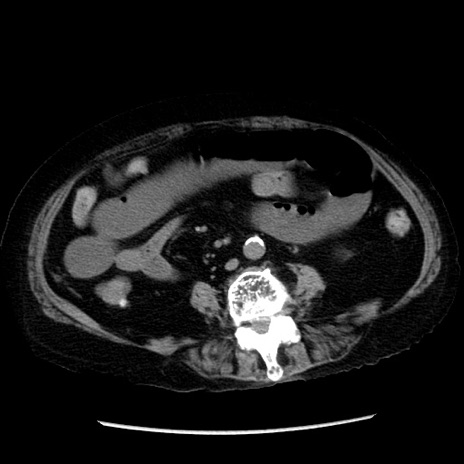

症例14(横断像)

【症例】 90歳代女性

【主訴】 腹痛・嘔吐

【現病歴】今朝から左側腹部痛を認めた。 経過観察していたが、嘔吐を認めたため来院。

【既往歴】 子宮癌術後

【身体所見】 意識清明、BP 127/54mmHg、P 98bpm Sp02 95%(RA)、BT 35.8°C、腹部平坦・軟腸ぜん動音聴取良好、右下腹部圧痛(+) 反跳痛なし

【データ】WBC 9800、CRP 0.46